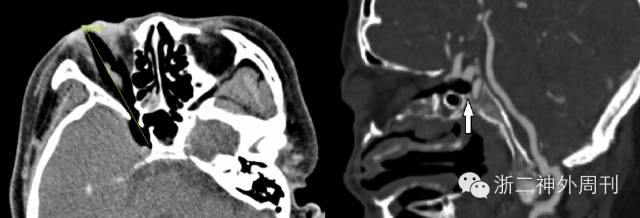

术后头颅MRI检查见右侧眼眶深部混杂信号,放射科报告考虑:1.窦道血肿;2.眶壁肿胀组织;3.不排除少量异物残留可能(图5)。考虑再手术探查的难度及风险,与家属沟通后建议密切随访观察。患者经抗炎治疗,创口愈合可,异物拔除1周后出院。

图5. 术后MRI检查,可疑少量异物残留。

一个月后患者因接连两次突发口鼻大出血(总出血量约达800~1000ml)再次急诊入院。查体示急性休克病容,予抗休克处理后行急诊头颅CT及CTA检查,提示右侧颈内动脉假性动脉瘤伴眼眶内异物残留(图6)。

图6. CT及CTA提示眶后异物残留,右颈内动脉假性动脉瘤。